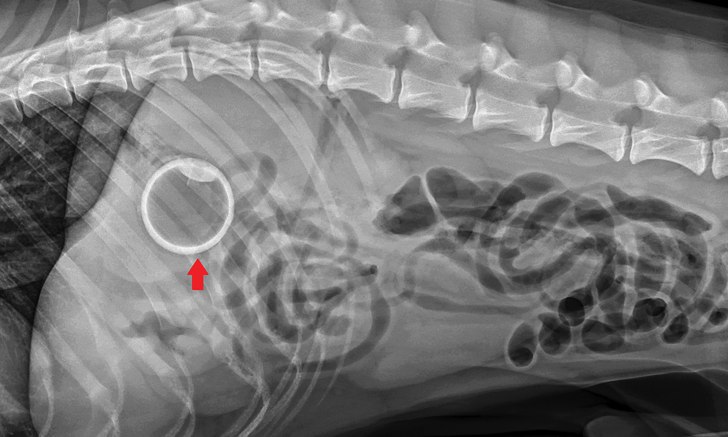

В желудке визуализируется рентгеноконтрастное, четко определенное, центрально заполненное газом инородное тело: теннисный мячик!